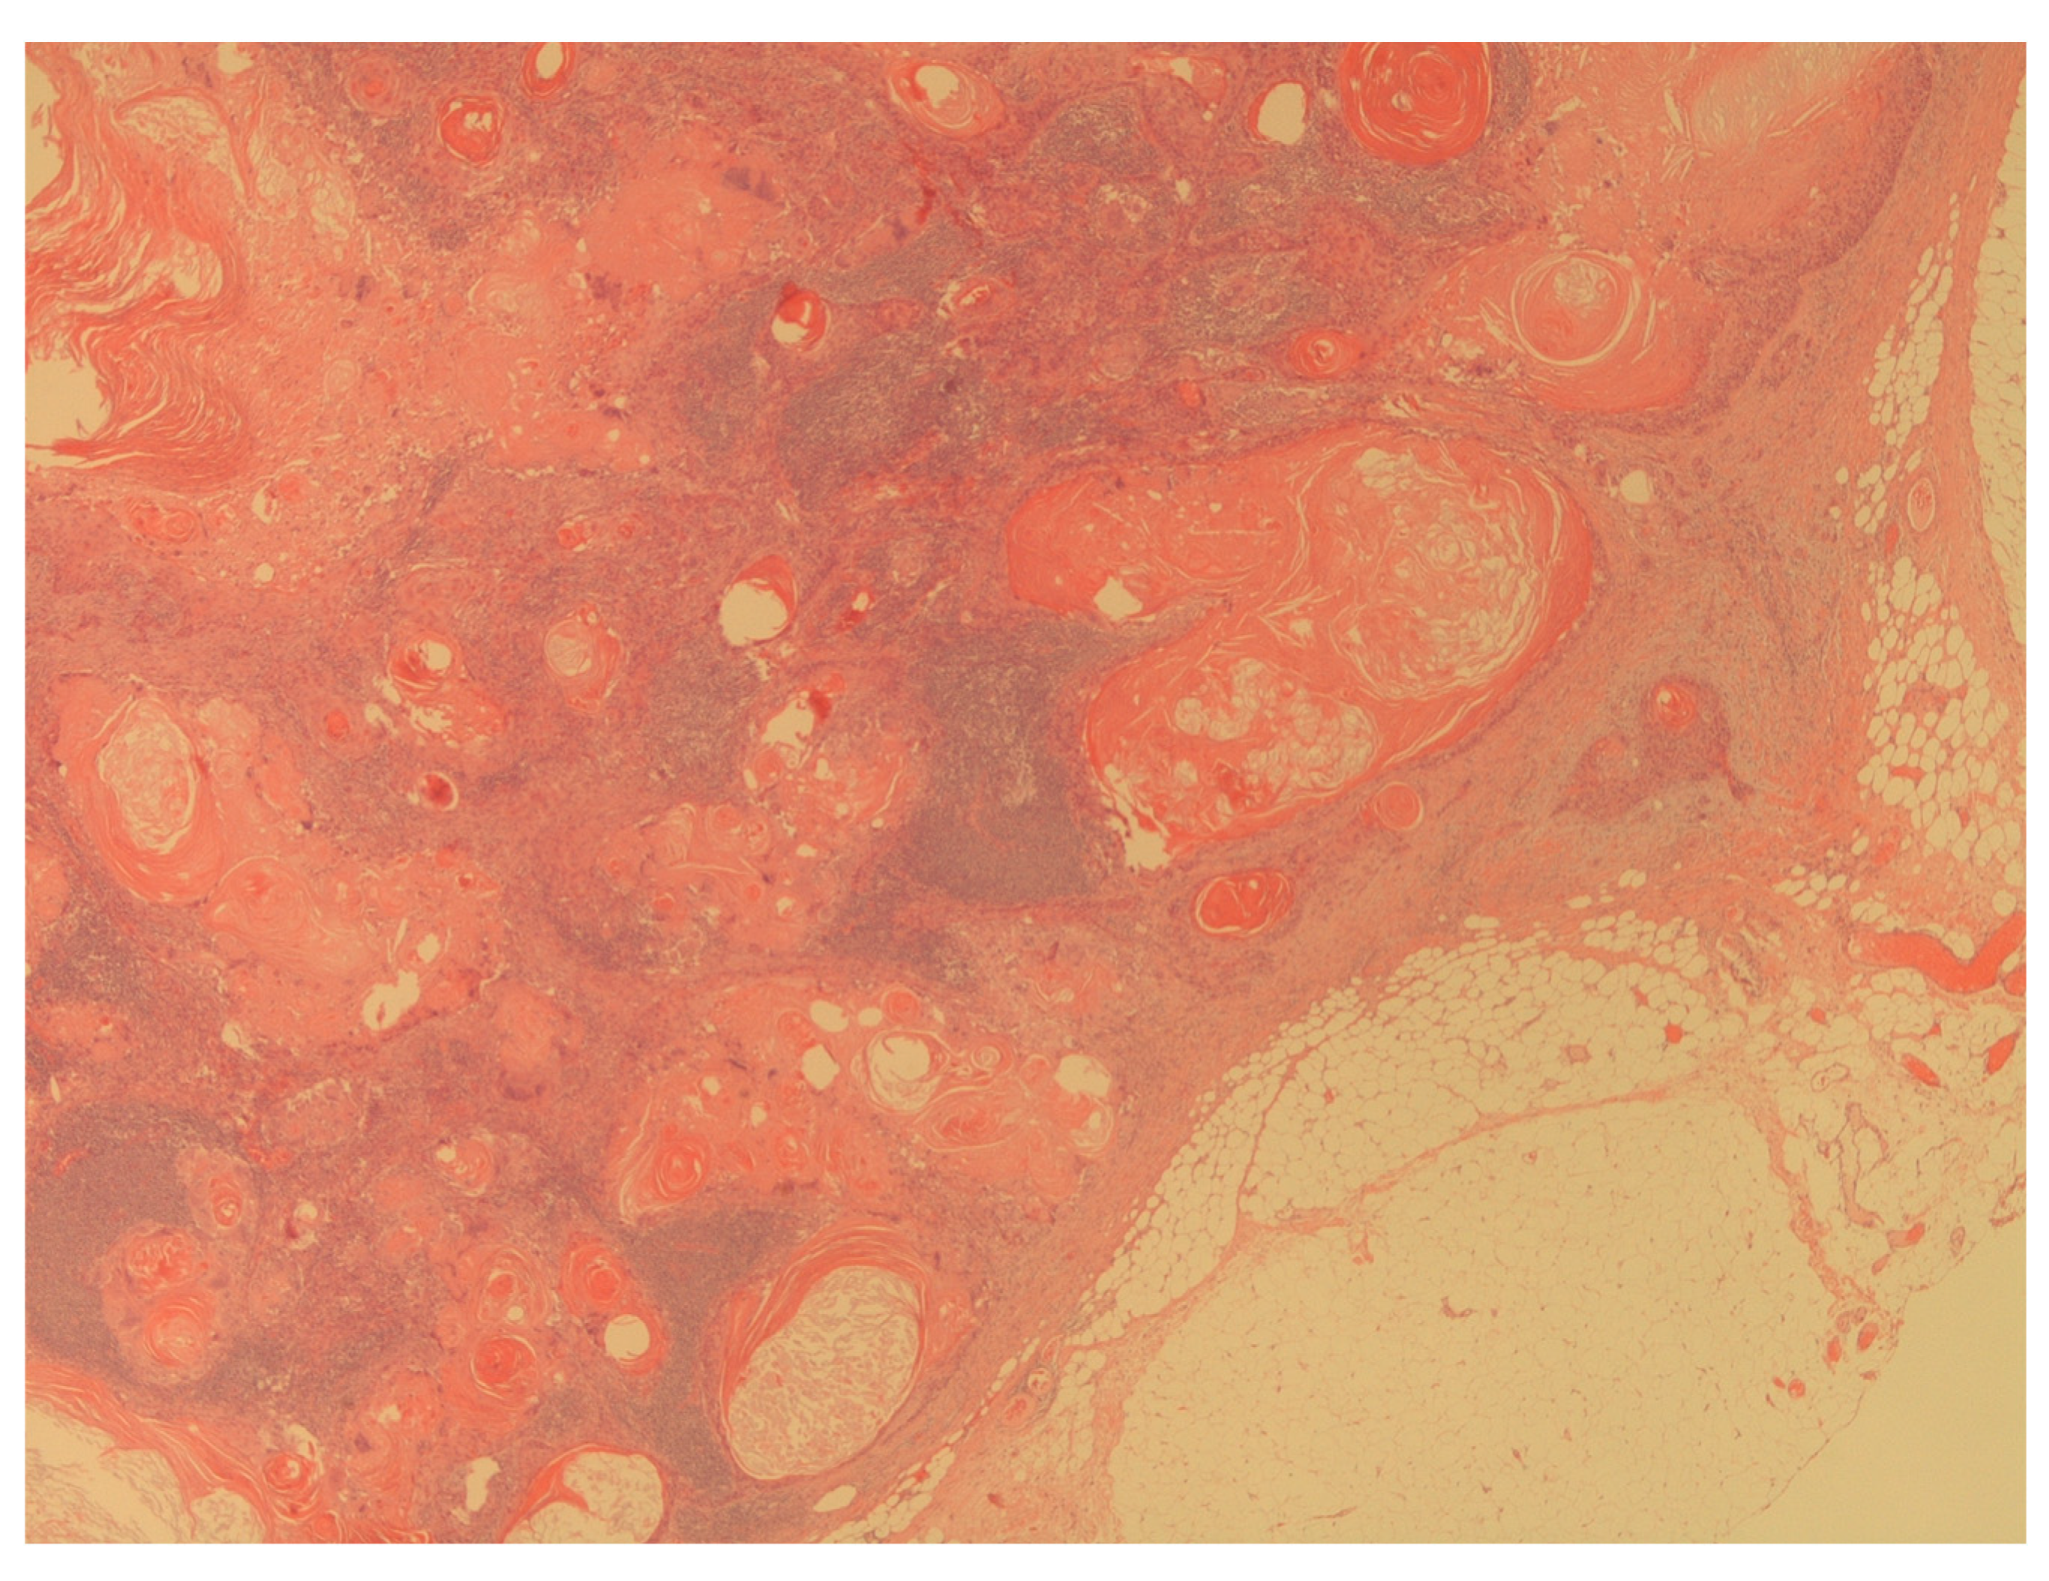

Figure 4. The figure shows a massive lymph node metastasis from squamous cell carcinoma (H&E; 20X).